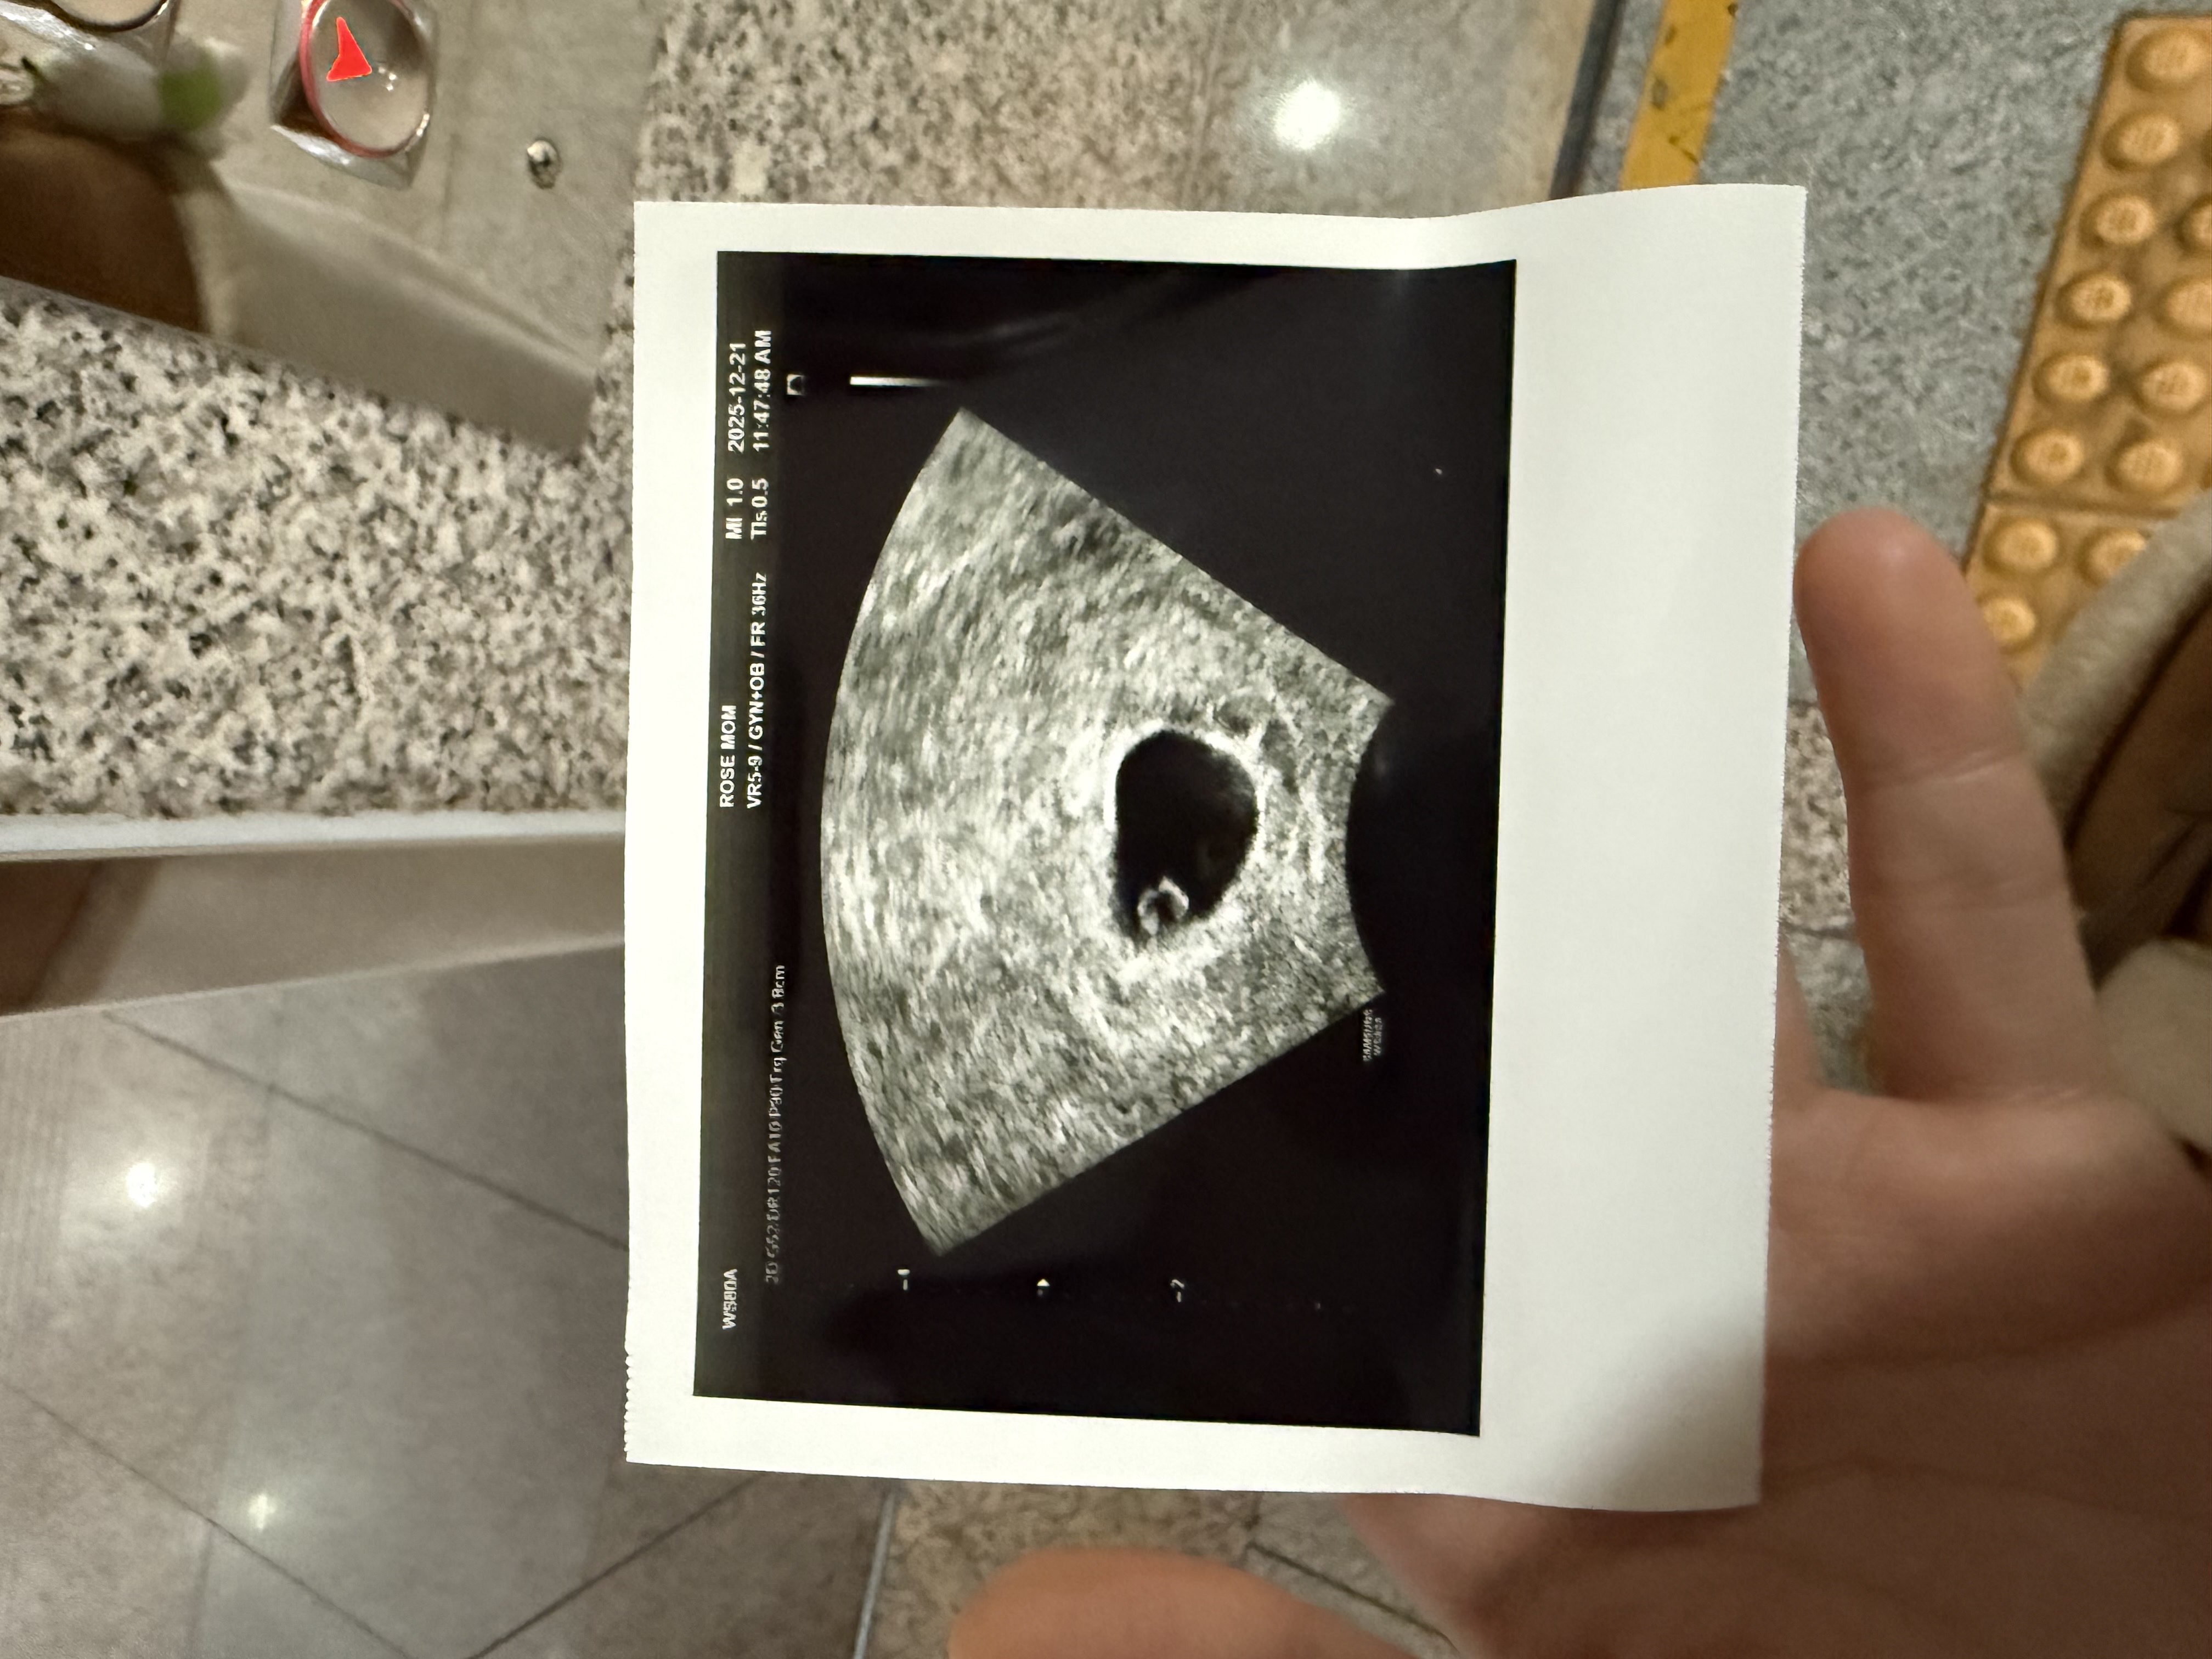

어제 저녁8시에 흐르는 느낌 들어서 봤더니 팬티에 피가 좀 많이 묻어 있길래 불안해서 오늘 산부인과 갔다 왔는데 괜찮다고 하네요 휴 화요일에 아기집만 보고 왔었는데 낭황까지 보고 와서 마음이 편해졌러요 ㅠㅠ